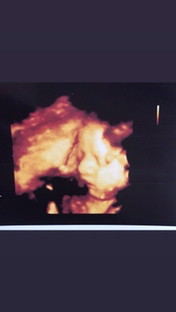

น้องมาวินมารายงานตัวค่ะ น้องอายมากเอาทั้งมือทั้งเท้าบังหน้า ต้องซาวนานๆถึงจะเห็นหน้า